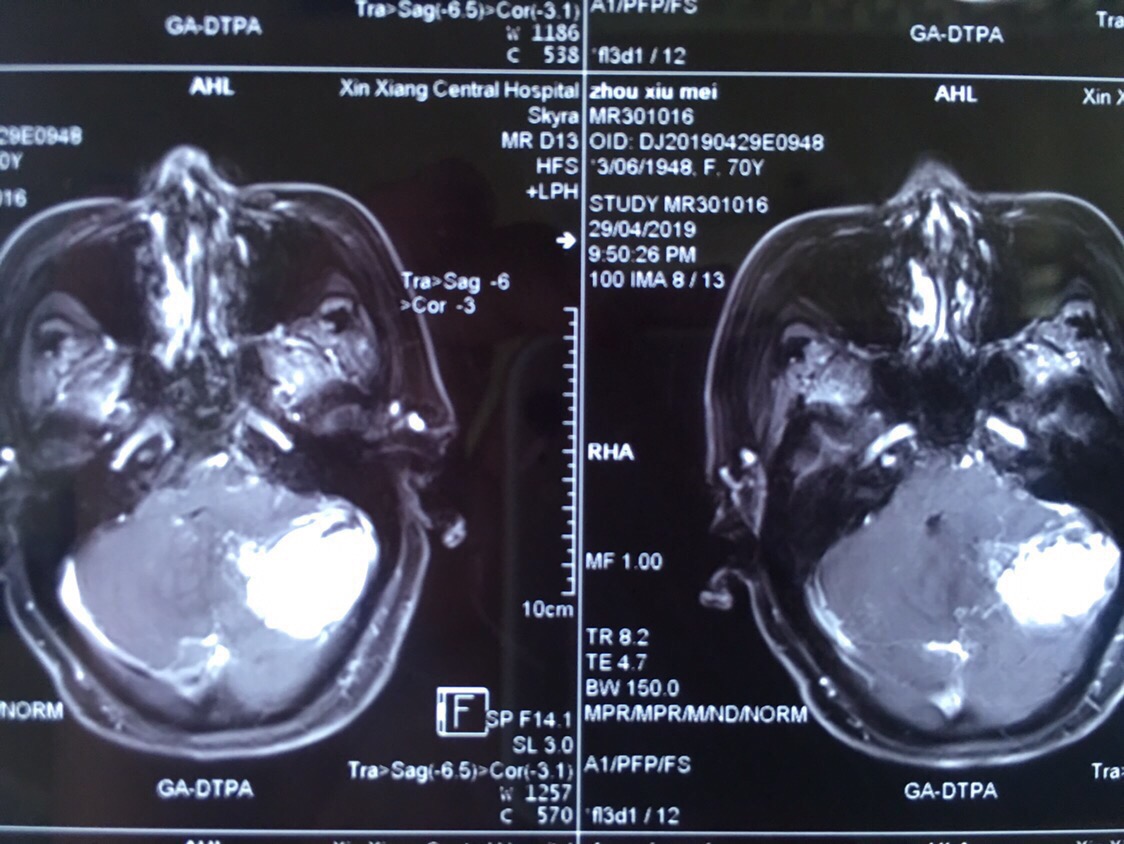

患者周某,女,70岁,以“间断头痛伴恶心呕吐五天”为主诉入院。既往患有高血压病3年,糖尿病3年,冠心病2年,控制情况一般。查体:神志模糊,精神差,可对答,回答正确,能完成简单指令性动作,反应迟钝,双瞳孔等大等圆,直径约3mm,光反射灵敏。指鼻试验不准,轮替试验缓慢。跟膝胫试验不稳。病理反射未引出。诊断:1.左侧小脑实性血管母细胞瘤,2.梗阻性脑积水,3.高血压病,4.冠心病,5.2型糖尿病。

增强轴位

增强冠位